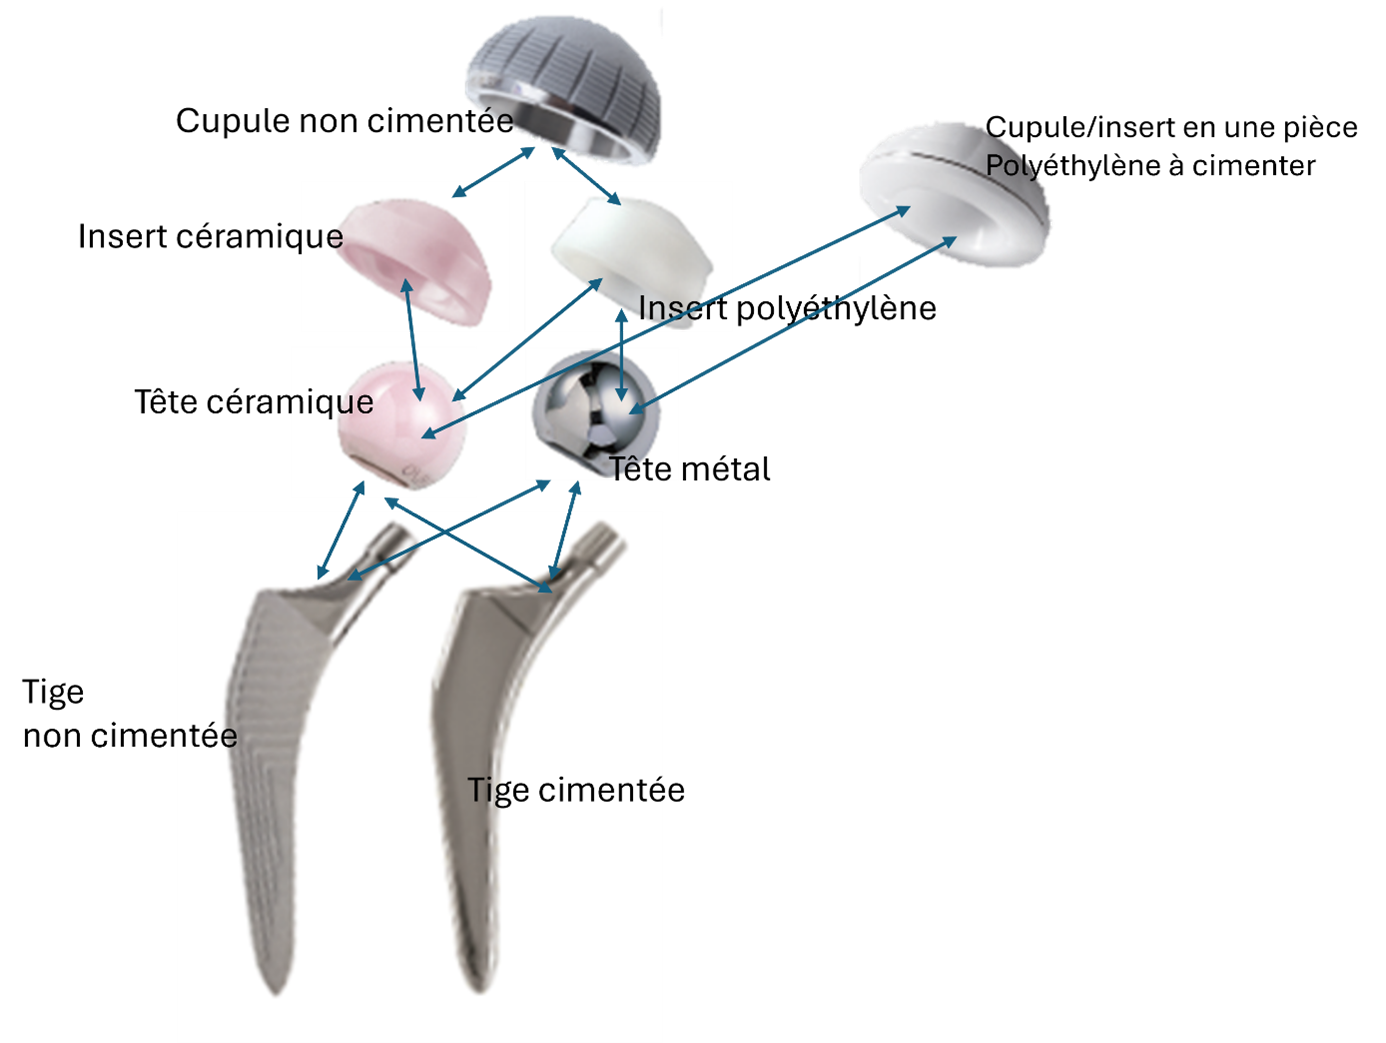

Une PTH remplace les surfaces articulaires usées :

- Cupule + insert côté bassin.

- Tige + tête côté fémur.

On distingue :

- Les pièces fixes : tige et cupule.

- Les pièces mobiles : tête et insert.

Les différentes combinaisons possibles:

De quels matériaux sont faites les prothèses ?

La tête de la PTH est soit en céramique soit en métal.

L’insert de la cupule est soit en polyéthylène soit en céramique.

Les matériaux utilisés pour les pièce fixes encrées dans l’os varient selon la nature de la fixation : cimentée ou non cimentée.

Actuellement la plupart des tiges et cupules non cimentées sont en alliage de titane souvent revêtu d’une couche d’hydroxyapatite (sur le schéma ci-dessus aspect gris-mat de la tige).

Les tiges cimentées sont en acier inox médical, aujourd’hui les cupules sont rarement cimentées, il existe des cupules cimentées entièrement en polyéthylène (l’insert et la cupule ne font qu’un) et des cupules en acier (nécessitant un insert) à cimenter.